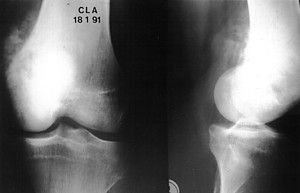

Technique Allogreffe cartilagineuse massive d'un genou en totalité selon la technique de D. Poitout , M. Lempidakis CHU Nord - Marseille , M. Bernat CHU Nord - Marseille , G. Martin CHU Nord - Marseille , D.G. Poitout CHU Nord - Marseille N°40 - Janvier 1995 ● 5 min de lecture